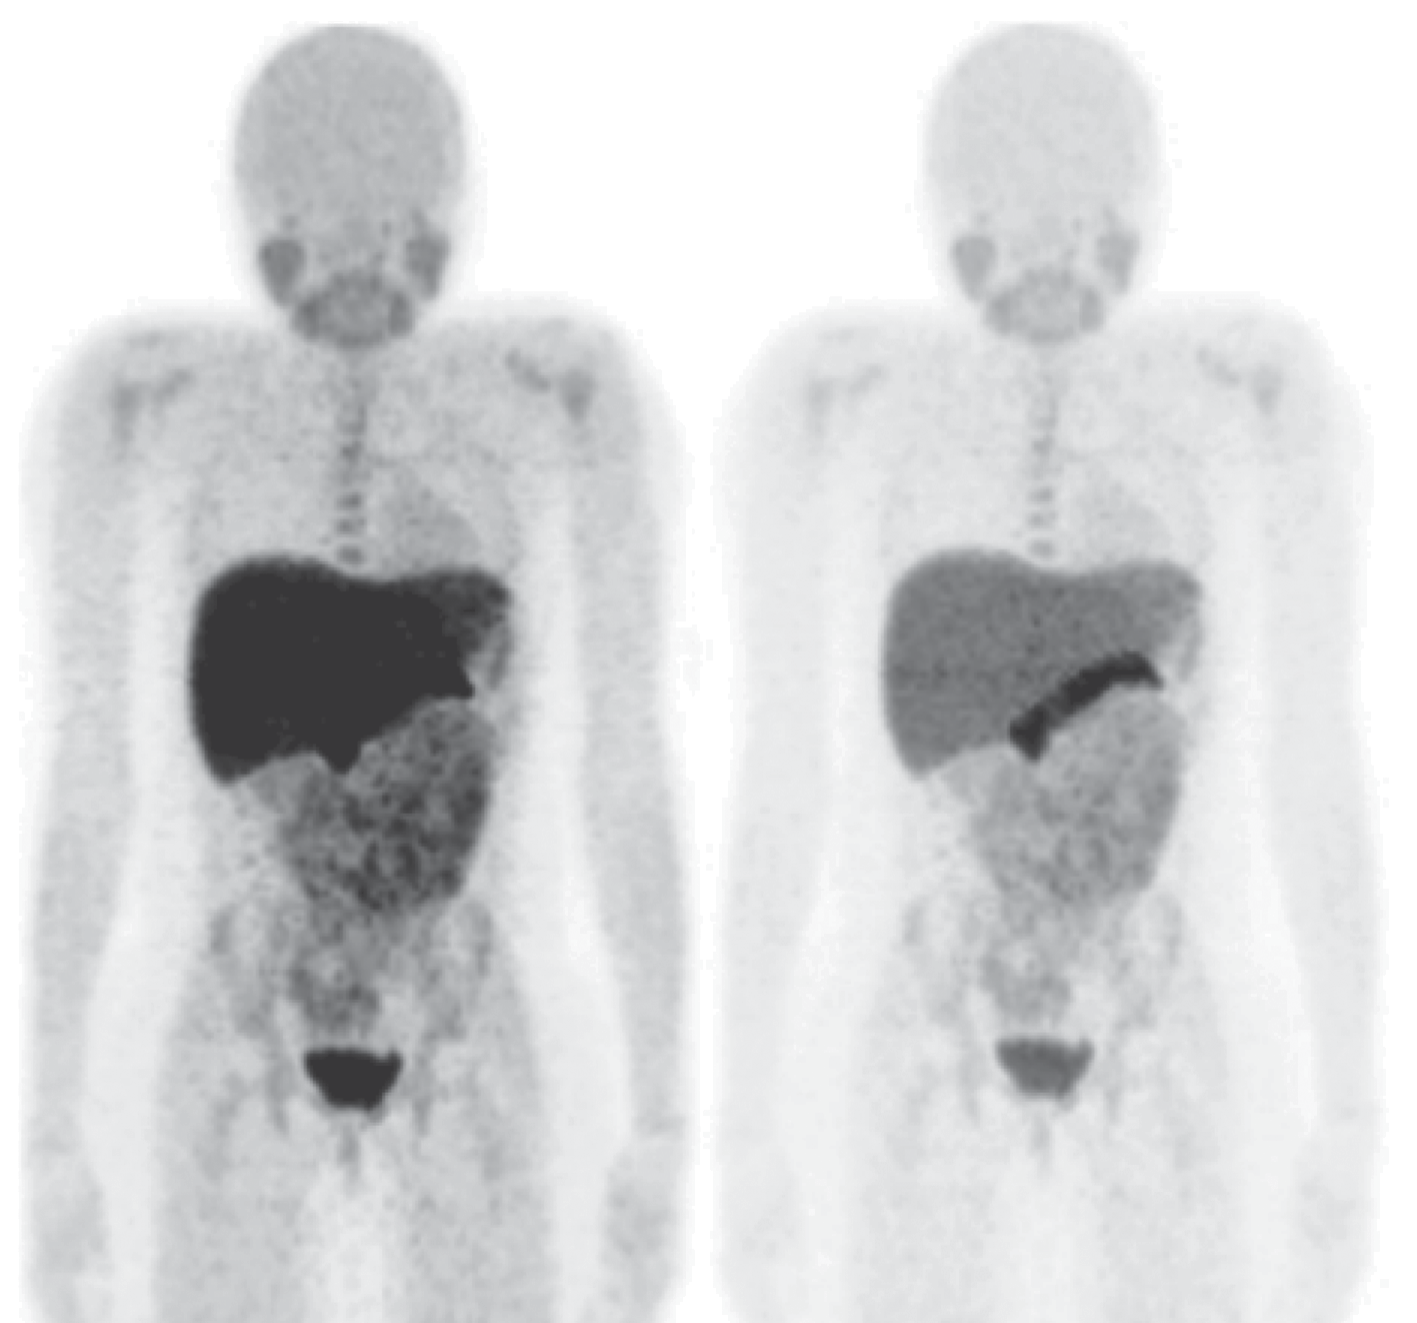

To date, the most common drug for the diagnosis of cancer tumors is [18F]-fluorodeoxyglucose, an radiopharmaceuticals for positron emission tomography diagnostics using the fact of increased glucose metabolism by cancer cells. At the same time, there are a number of cases where an approach based on glucose derivatives is not applicable. In many cases, inflammation or other benign processes are indistinguishable from tumor formations. For such cases of non-specificity of oncologies to glucose (not only tumor cells, but also healthy cells actively consume [18F]-fluorodeoxyglucose), the use of other metabolic pathways is required, which, in the case of a specific tumor in this organ, will be specific to the radiopharmaceuticals used.